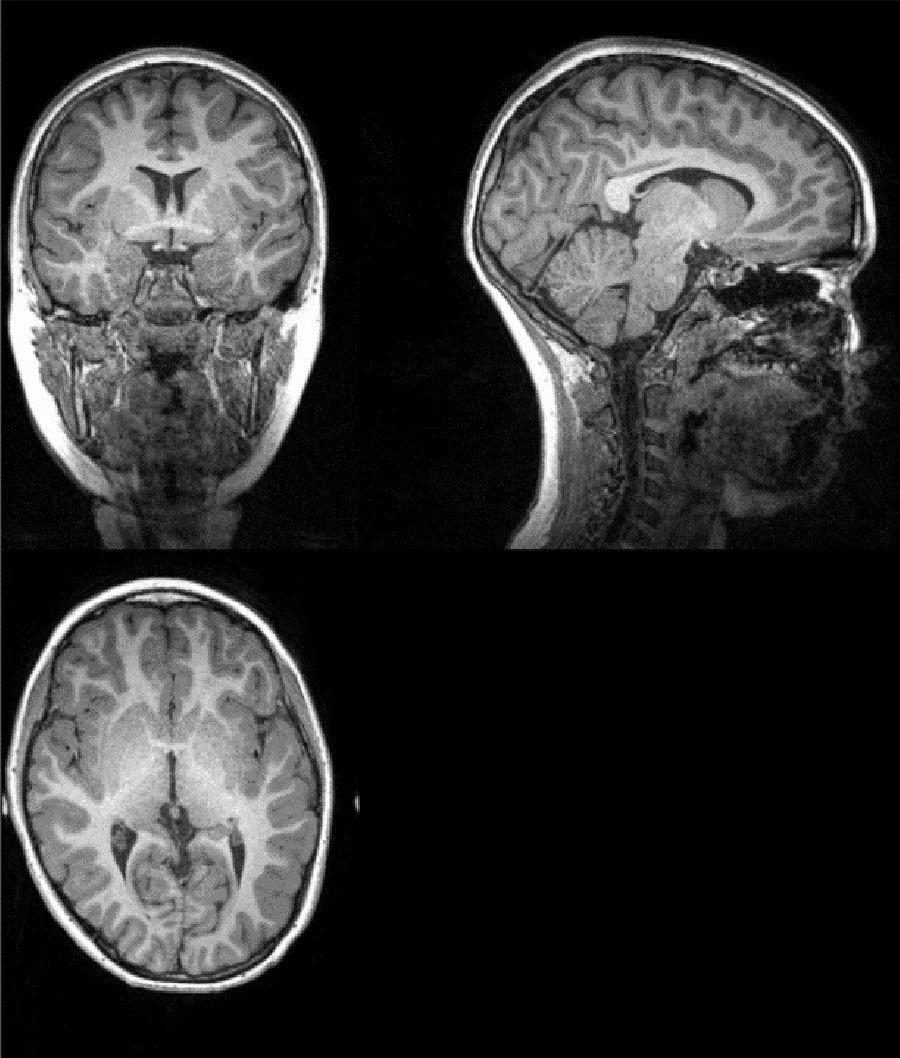

Los pacientes con COVID-19 que reciben oxígeno o experimentan fiebre muestran un menor volumen de materia gris en la red frontal-temporal del cerebro, según un nuevo estudio dirigido por investigadores de la Universidad Estatal de Georgia y el Instituto Tecnológico de Georgia (Estados Unidos).

El estudio, publicado en la revista `Neurobiology of Stress`, ha evidenciado que un menor volumen de materia gris en esta región del cerebro se asociaba a un mayor nivel de discapacidad entre los pacientes con COVID-19, incluso seis meses después del alta hospitalaria.

El análisis mostró que los pacientes con mayores niveles de discapacidad tenían un menor volumen de materia gris en los giros frontales superior, medial y medio en el momento del alta y seis meses después, incluso cuando se controlaban las enfermedades cerebrovasculares.

El volumen de materia gris en esta región también se redujo significativamente en los pacientes que recibían oxigenoterapia en comparación con los que no la recibían. Los pacientes con fiebre presentaron una reducción significativa del volumen de materia gris en los giros temporales inferior y medio y en la circunvolución fusiforme en comparación con los pacientes sin fiebre. Los resultados sugieren que la COVID-19 puede afectar a la red frontal-temporal a través de la fiebre o la falta de oxígeno.

También se observó una reducción de la materia gris en los giros frontales superior, medial y medio en los pacientes con agitación en comparación con los pacientes sin agitación. Esto implica que los cambios en la materia gris de la región frontal del cerebro pueden ser la base de las alteraciones del estado de ánimo que suelen presentar los pacientes con COVID-19.